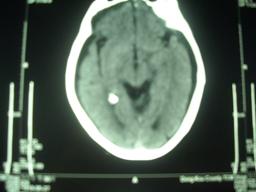

外伤性硬膜下积液(tse)又名硬膜下水瘤,是颅脑外伤蛛网膜撕裂,使脑脊液在硬膜下积聚所致.近年来,国内外学者注意到tse可转变为慢性硬膜下血肿(csdh)

tse和csdh作为两个不同的颅脑疾病,分别由mayo和virchow于1894年和1857年首先报道,tse的发病机理是颅脑外伤时,脑组织在颅内剧烈移动,外侧裂池、视交叉池或脑表面的蛛网膜被坚固的颅骨撕破形成一个单向活瓣,使脑脊液由蛛网膜下腔向硬膜下腔积聚而成。而csdh的发病原因仍不清楚,多数学者认为血肿是头部损伤引起,也有认为可能与血管性或出血疾病有关。1979年,日本学者yamada等首先报道3例类似的演变。

tse演变为csdh的发生率各家报道不一,从0~58%,日本学者的报道其发生率较高;关于病变演进的机理,目前仍有争议,一些学者认为是tse发生后,硬膜下积液的积聚使脑实质和硬膜的距离增大,桥静脉被牵拉变长,破裂出血所至,它好发于老年人,可能与老年人脑萎缩后硬膜下腔增大有关。

另有学者则反对上述观点,认为csdh可能并非由tse转变而来,而是由急性硬膜下血肿液化所至,认为ct中的低密度可能是csdh,而不是tse。他们观察到,在tse的积液中,往往存在血性液体或者呈淡黄色的脑脊液。但这一观点无法解释的是,tse往往在伤后数日或一周内即形成,而急性硬膜下血肿变为低密度灶,往往需2周时间.